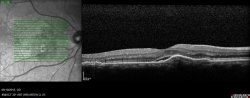

- Le diagnostic se fait à l’aide de photographies du fond d’œil, de clichés en autofluorescence et d’un OCT.

- Bilan : Le diagnostic se fait au fond d’œil et à l’OCT, et doit être confirmé par une OCT-angiographie ou une angiographie à la fluorésceine et parfois une angiographie au vert d’indocyanine lors du bilan initial.

- Un OCT s’il y a un œdème maculaire.

- Macula bombée est une anomalie décrite récemment par le Professeur A. Gaudric. Il s’agit d’un épaississement en dôme de la sclére au niveau de la macula. Elle peut entrainer une baisse de vision. Le diagnostic se fait à l’OCT. Un décollement séreux rétinien peut se voir au sommet du dôme. Il n’y a pas de traitement.

- Le fovéoschisis est un clivage entre les différentes couches de la rétine au niveau de la macula. Il évolue de façon très lente et n’entraine pas forcement de baisse de vision. Le diagnostic se fait à l’OCT. La surveillance est de rigueur. Si le fovéoschisis entraine une baisse de vision notable, une chirurgie pourra être envisagée à type de vitrectomie+/-pelage+/-gaz.

Une surveillance ophtalmologique régulière, au moins annuelle, est donc nécessaire en cas de myopie forte. Le bilan ophtalmologique doit comporter un examen clinique standard avec l’acuité visuelle corrigée de loin et de prés, la prise du tonus intra-oculaire, l’examen des segments antérieurs à la lampe à fente (analyse du cristallin notamment) et un fond d’œil dilaté. De plus un OCT maculaire permettra dans de nombreux cas un diagnostic plus précis.

Il se fait au fond d’œil, il est confirmé à l’OCT et à l’angiographie. L’angiographie à la fluorescéine permet d’éliminer une autre maladie et de repérer le point de fuite ; dans certains cas l’angiographie au vert d’indocyanine est indispensable pour guider le traitement ou éliminer un néovaisseau choroïdien.